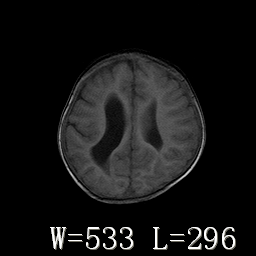

标题: PED3252:脑室增大。

女,3岁,3岁不会说话,阵发性抽搐、自伤。

考虑为梗阻性脑积水(中脑导水管狭窄)。

侧脑室不规则,前后角尖角样,脑白质较少:考虑灰质发育不良可能

倒数第3附图不是这个病人的吧!考虑脑白质发育不良可能。

右侧额叶发育不良!

右侧额叶发育不良。

右侧额叶发育不良

考虑,脑发育不良,胼胝体发育不全?(图片不全,矢状位?)